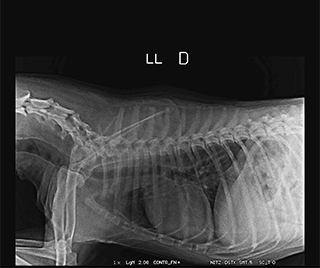

Radiologia Digital Direta / Digital Radiography

O treinamento aborda a geração das radiografias, a edição digital das imagens, e também a

escolha adequada de técnicas radiográficas como kilovoltagem, corrente elétrica e tempo de exposição.